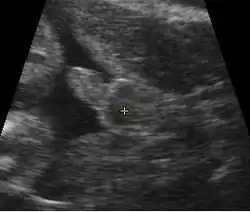

Um saco gestacional pode ser visto de forma confiável na ultrassonografia transvaginal por volta de 5 semanas de idade gestacional (aproximadamente 3 semanas após a ovulação). O embrião deve ser visto quando o saco gestacional mede 25 mm, por volta de cinco semanas e meia.[10] O batimento cardíaco geralmente é visto na ultrassonografia transvaginal quando o embrião mede 5 mm, mas pode não ser visível até que o embrião atinja 19 mm, por volta de 7 semanas de idade gestacional.[5][11][12] Coincidentemente, a maioria dos abortos espontâneos também ocorre até a 7ª semana de gestação. A taxa de aborto, especialmente o aborto ameaçado, cai significativamente após a detecção de batimento cardíaco normal e após 13 semanas.[13]

-

Conteúdo da cavidade do útero visto em aproximadamente 5 semanas de idade gestacional -